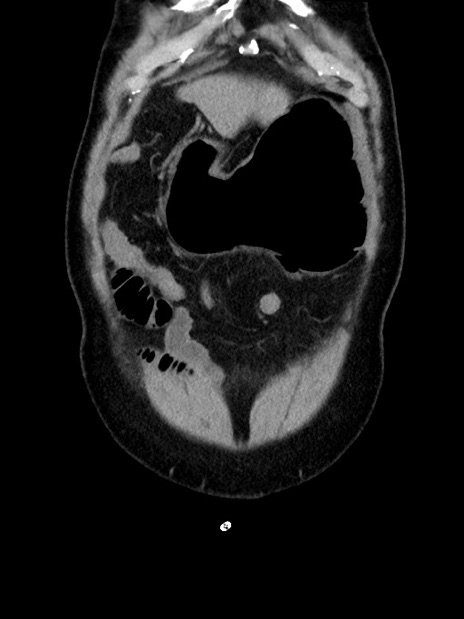

症例35(冠状断像)

症例

【症例】70歳代 男性

【主訴】腹部膨満、嘔吐

【現病歴】昨日より腹部膨満感出現。本日増悪し、仙痛出現。嘔吐あり、受診。

【既往歴】糖尿病、胆摘後

【身体所見】BP 149/80mmHg、HR 74/min、BT 35.9℃、腹部:膨満、軟、圧痛なし。腸雑音減弱あり。上腹部正中切開瘢痕あり。

【データ】WBC 13500、CRP 1.72